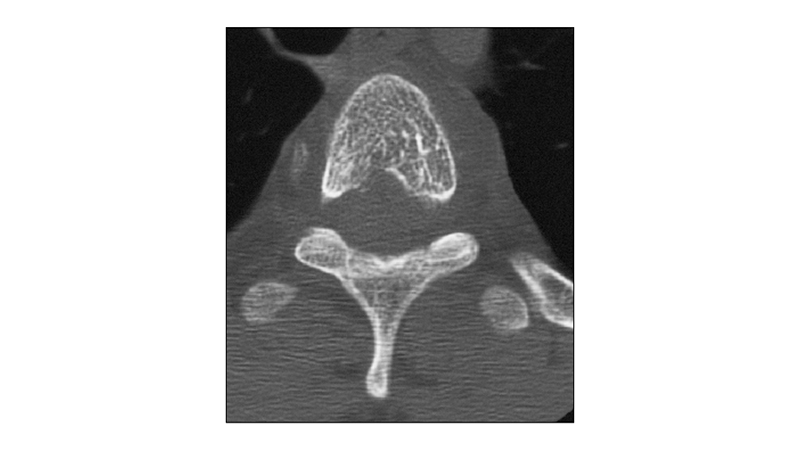

Εικόνα 7: Αξονική τομογραφία, στο επίπεδο του Θ3 μετά τον εμβολισμό: Διακρίνεται το εκμαγείο της κυανοακρυλικής κόλλας.